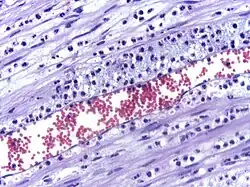

The cytoskeletons of the leukocytes are reorganized in such a way that the leukocytes are spread out over the endothelial cells. In this form, leukocytes extend pseudopodia and pass through gaps between endothelial cells. This passage of cells through the intact vessel wall is called diapedesis.[3] These gaps can form through interactions of the leukocytes with the endothelium, but also autonomously through endothelial mechanics.[4] Transmigration of the leukocyte occurs as PECAM proteins, found on the leukocyte and endothelial cell surfaces, interact and effectively pull the cell through the endothelium. Once through the endothelium, the leukocyte must penetrate the basement membrane. The mechanism for penetration is disputed, but may involve proteolytic digestion of the membrane, mechanical force, or both.[5] The entire process of blood vessel escape is known as diapedesis. Once in the interstitial fluid, leukocytes migrate along a chemotactic gradient towards the site of injury or infection.